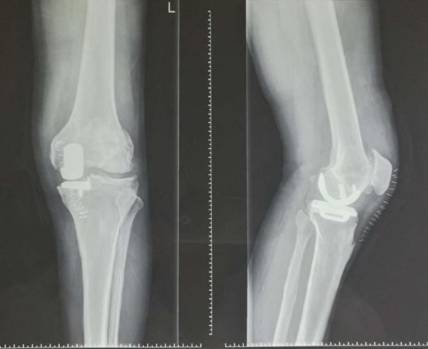

全膝表面置换术治疗重度骨关节病

优点:疗效可靠,膝关节病的最终解决方案。

术前术后对比

全膝关节翻修术

全髋关节翻修术